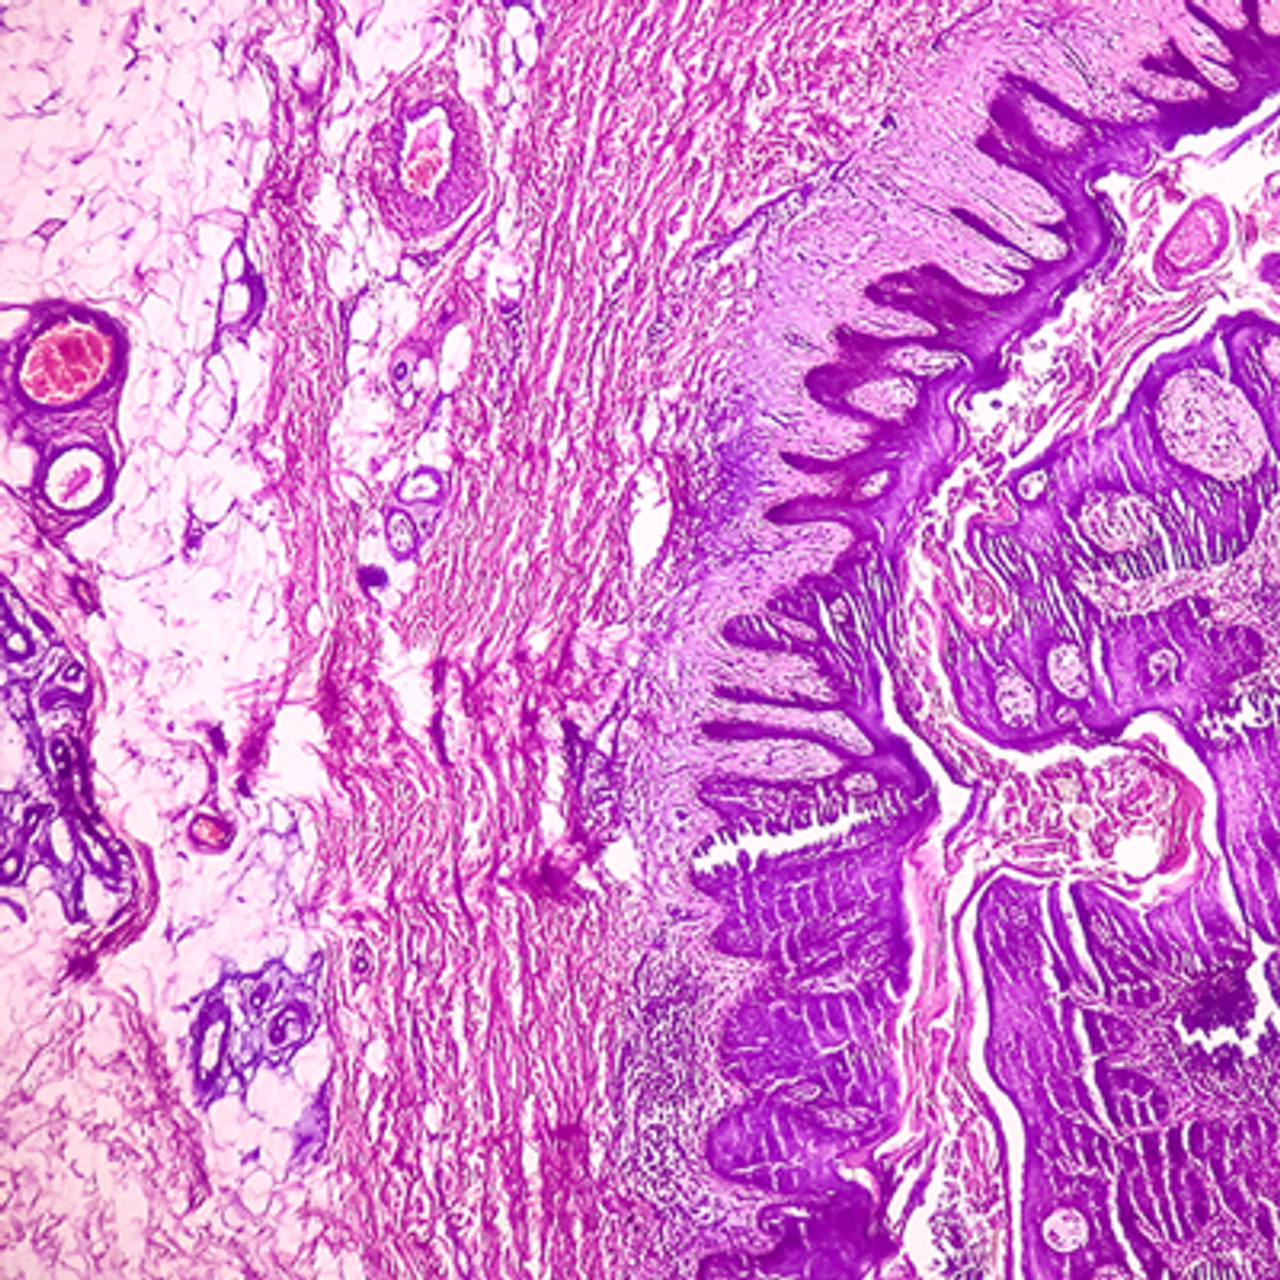

Oakstone Dermatopathology 2025